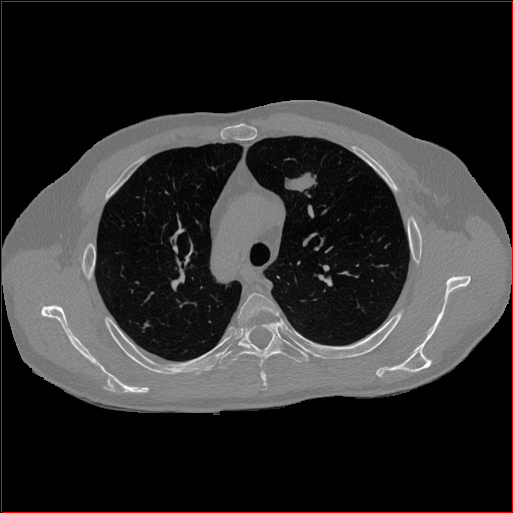

Figure 2: Qualitative comparison across axial (top row), sagittal (middle row), and coronal (bottom row) views. Columns correspond to different methods. MAISI-DDPM and MAISI-v2 in this figure are unconditional synthesis which do not use ControlNet or segmentation maps.

Qualitative Evaluation:

Figure 2 presents representative slices from the axial, sagittal, and coronal planes. GenerateCT (hamamci2024generatect) is a 2D model, so it lacks inter-slice consistency, leading to poor image quality in the sagittal and coronal views. MedSyn (xu2024medsyn) produces noticeably blurry results with mosaic-like artifacts, such as region inside the red box. HA-GAN (sun2022hierarchical) generates visually sharp images but with mosaic-like artifacts, such as region inside the red box. Also, its voxel spacing is not available, which limits its applicability in real-world medical imaging tasks. Moreover, all three methods are restricted to synthesizing small anatomical regions. In contrast, both MAISI and MAISI-v2 are capable of generating high-quality 3D volumes that span larger body regions while preserving fine anatomical details and realistic structure.